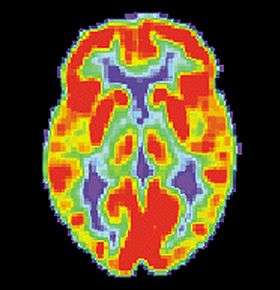

False memories and PET scans

A follow-up to the previous research was conducted by Daniel L. Schacter and colleagues. Similar to the study by Henry L. Roediger and Kathleen McDermott, subjects were read a list of associated words before they went into the PET scanner. During the first scan, subjects would make recognition judgments to determine what were the previous presented words.[4] During the second scan, subjects had to make judgments about words that were not presented. For example: bed, rest, dream, tried, and awake would be in the list but not the word "sleep". As with the study by Henry L. Roediger and Kathleen McDermott, subjects claimed to remember similar amounts of non-presented words as they did the words that were actually presented.[4] The researchers noted that brain activity during the true and false recognition tasks were very similar. Monitoring the blood flow in the brain revealed there were in the left medial temporal lobe for both veridical and illusory recognition.[18]

That is not to say that there were not differences. While monitoring blood flow in the brain during false recognition, a part of the frontal lobe that is thought to be a key monitor of memories actually showed greater activity when presented with a false recognition than with a true one.[4] There seemed to be some discrepancy as subjects attempted to scrutinize the out-placed words, but were overcome by powerful memory illusion.[4] This study demonstrates the ability of technology to help researchers understand to a greater extent the power of false memories.

PET Normal brain

PET Alzheimer's disease